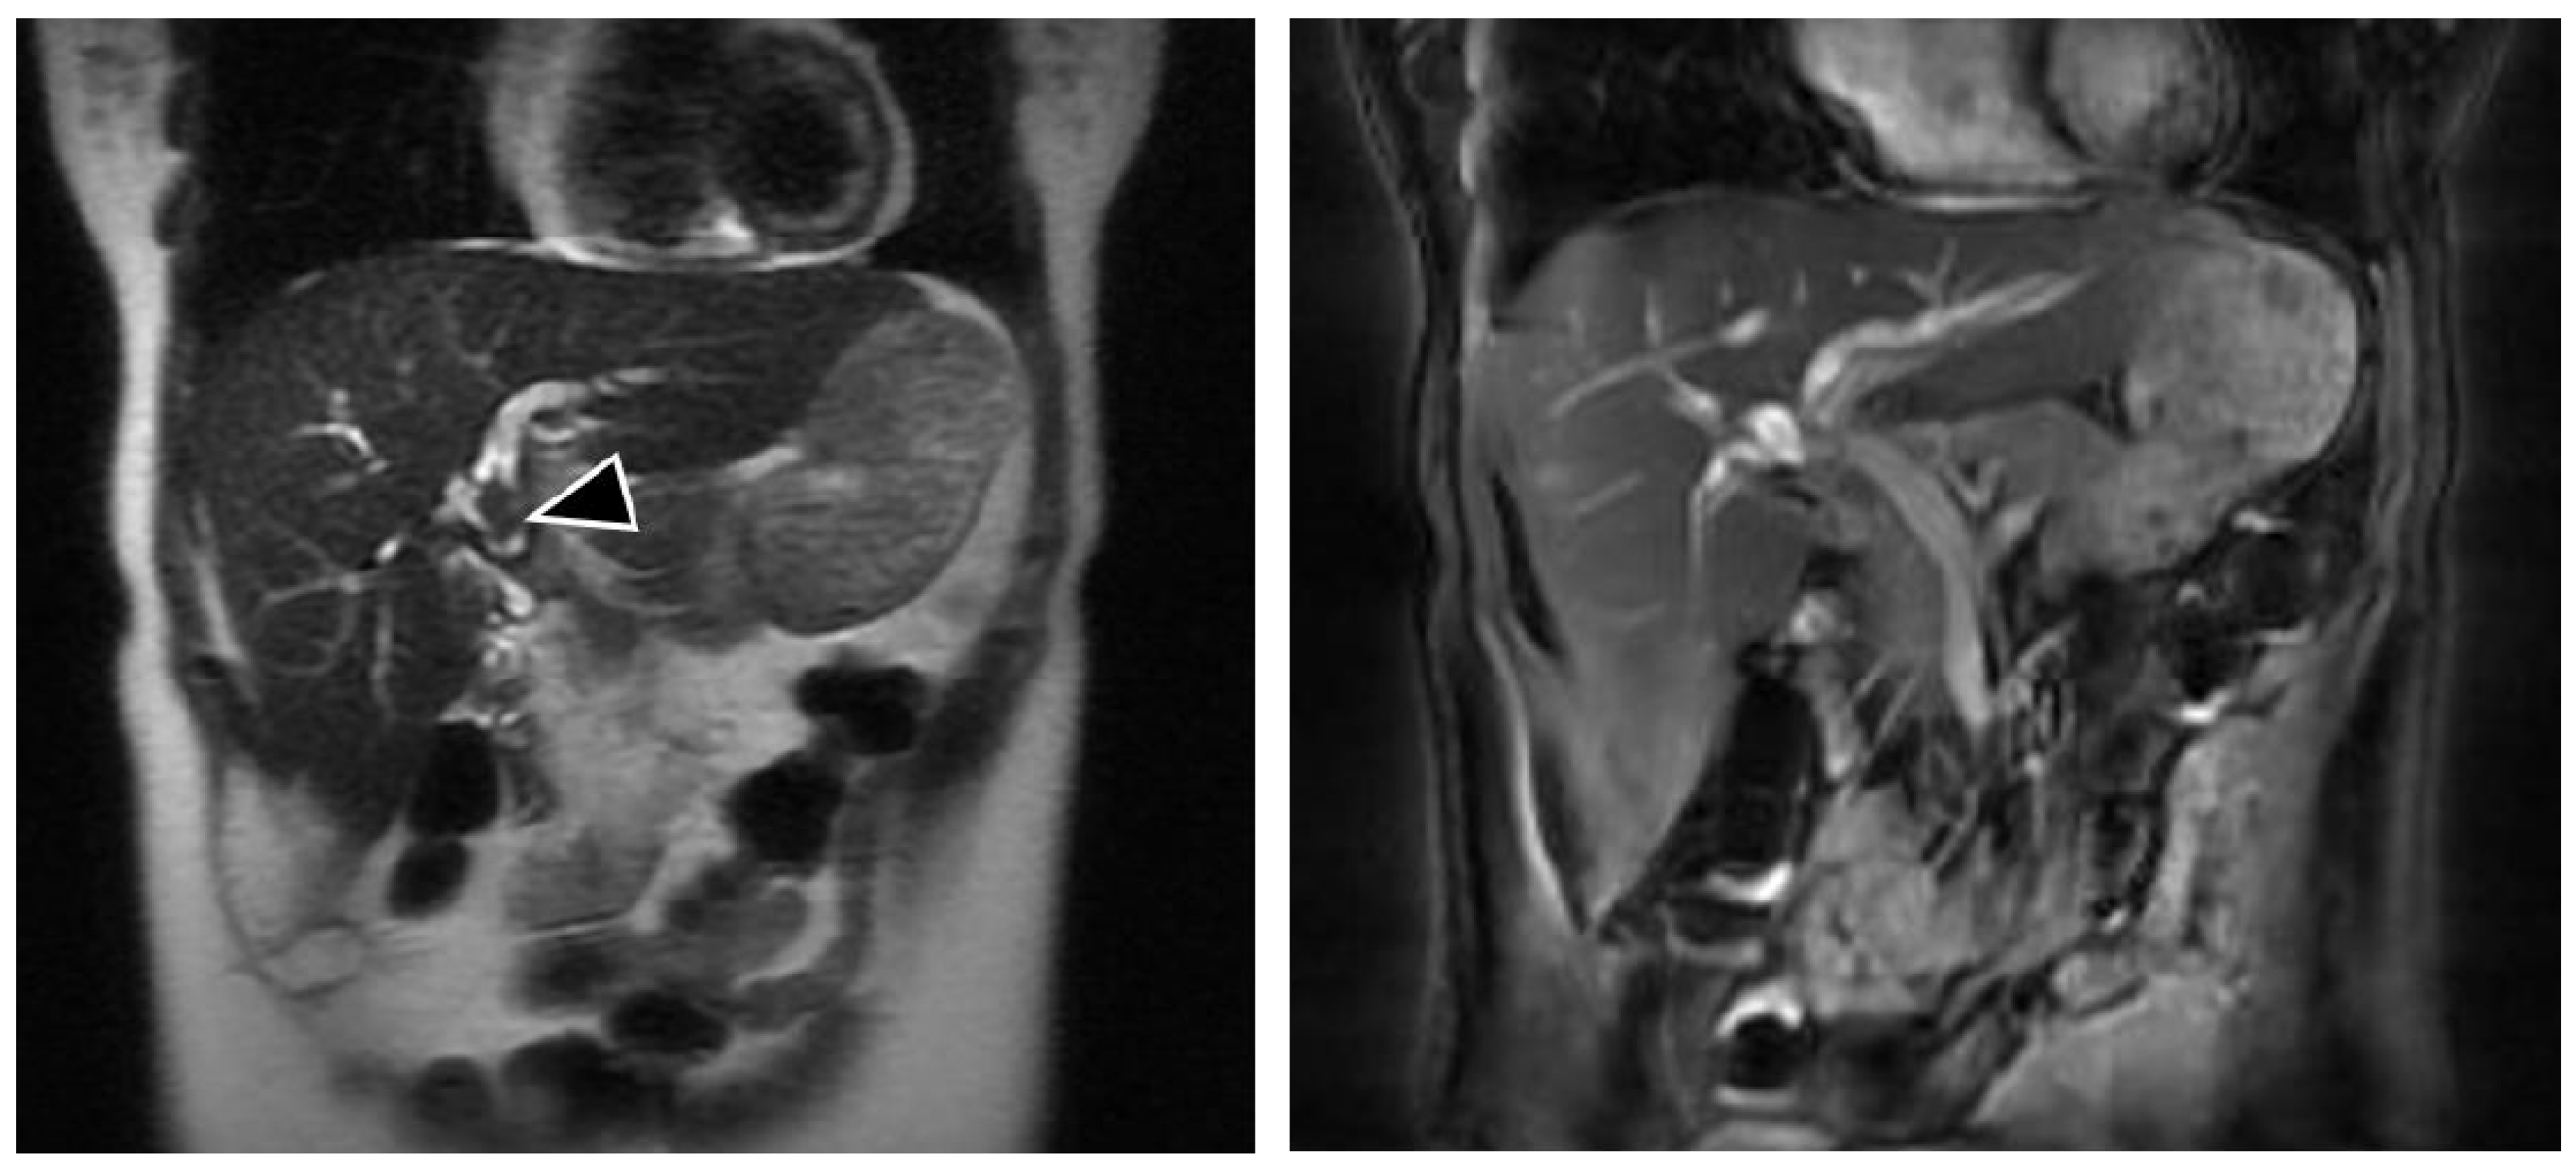

We report a case of a 50-year-old overall healthy female with history of biliary injury during cholecystectomy repaired with RYHJ 25 years ago as well as open hepatic adenoma resection and splenectomy 4 years ago. Her follow-up was uneventful until 2 years ago when she started with episodes of abdominal pain localized in the right upper quadrant, associated with fever and non-bilious emesis, which were managed by her local physician with analgesics and antibiotics. In the previous days, the pain had dramatically intensified and she was referred to our center for surgical evaluation. Physical examination revealed abdominal pain on deep palpation in the lower right hypochondrium, with negative peritoneal signs. Vital signs were all in normal ranges for her age. Laboratory analyses were as follows: leukocytes 13.9 cells/mm3; neutrophils 8.6 cells/mm3; total bilirubin: 0.7 mg/dL; alanine transaminase: 173 U/L; aspartate transaminase: 130 U/L; alkaline phosphatase: 1162 U/L, GGT 300 U/L, amylase: 300 U/L, and negative viral hepatitis panel. Magnetic resonance cholangiography (MRC) revealed intrahepatic duct dilation and lithiasis (Figure 1).

Figure 1.

Magnetic resonance cholangiography showing the filling defect in the hepatic bile duct (arrow).